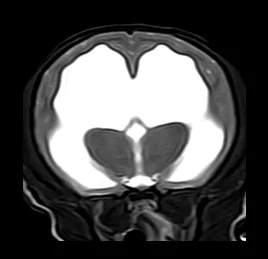

• 뇌수두증